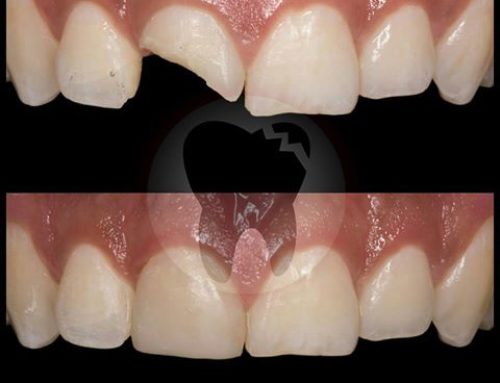

En dientes e implantes dejaremos tus dientes radiantes.